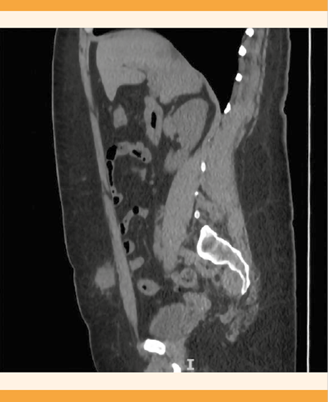

La tomografía abdominal reportó: útero con ausencia quirúrgica, hernia umbilical de 22 x 12 mm con contenido graso peritoneal y orificio herniario de 6 mm, posible tejido inflamatorio subcutáneo por debajo del saco herniario de 25 x 22 mm, con registro de densidad de 38 UH, tejido subcutáneo medial en la fosa iliaca derecha por arriba del músculo recto mayor de 22 x 19 mm, con registro de densidad de 21 UH. Figuras 1 y 2

Figura 2 Tomografía computada que muestra un tumor en el tejido celular subcutáneo de la fosa iliaca derecha (izquierda) y paraumbilical (derecha).

La resección quirúrgica y la histopatología son la base para el diagnóstico definitivo y tratamiento. Los estudios de imagen auxiliares pueden facilitar la identificación de este padecimiento sin alcanzar la certeza. La ecografía abdominal y transvaginal esclarecen las sospechas diagnósticas, sobre todo en la endometriosis pélvica. En la endometriosis de la pared abdominal los estudios de imagen de elección son la tomografía computada o la resonancia magnética; en la paciente del caso se optó por la primera. La tomografía computada permitió evaluar adecuadamente la localización y características de las lesiones y ofrecer la mejor aproximación quirúrgica.1,17,18